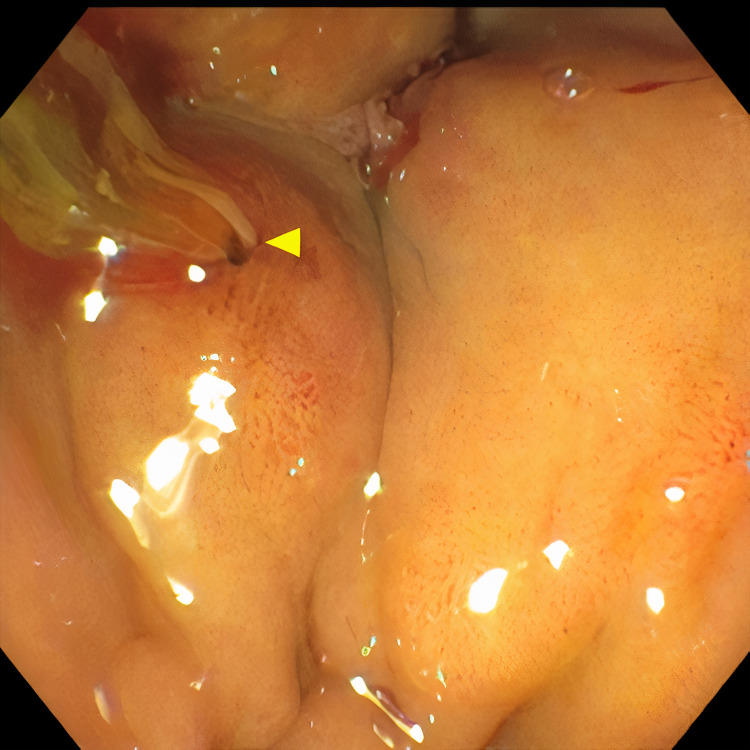

Pertinent labs include elevated white blood cells (13.5×10³/µL), total bilirubin (15.7 mg/dL), direct bilirubin (11.7 mg/dL), aspartate aminotransferase (98 U/L), and alanine aminotransferase (41 U/L). Urinalysis showed tea-colored urine. CT scan of the abdomen and pelvis revealed a collapsed gallbladder with CBD obstruction and bile duct dilation consistent with chronic inflammation. Endoscopic retrograde cholangiopancreatography (ERCP) was then performed which demonstrated cystic duct stone eroding into the common hepatic duct, hence the diagnosis of Mirizzi syndrome was made. Cholangioscopy confirmed the eroding stone, chronic inflammatory changes, and destruction of the bile duct. A cholecystoduodenal fistula with pus drainage was noted in the duodenal bulb. The patient was diagnosed with MS type V according to the ERCP findings. The stone was not amenable to endoscopic removal, but stone debris, clots, and pus (Figures 1–4) were swept. He was referred to the surgical team for cholecystectomy and repair of cholecystoduodenal fistula.